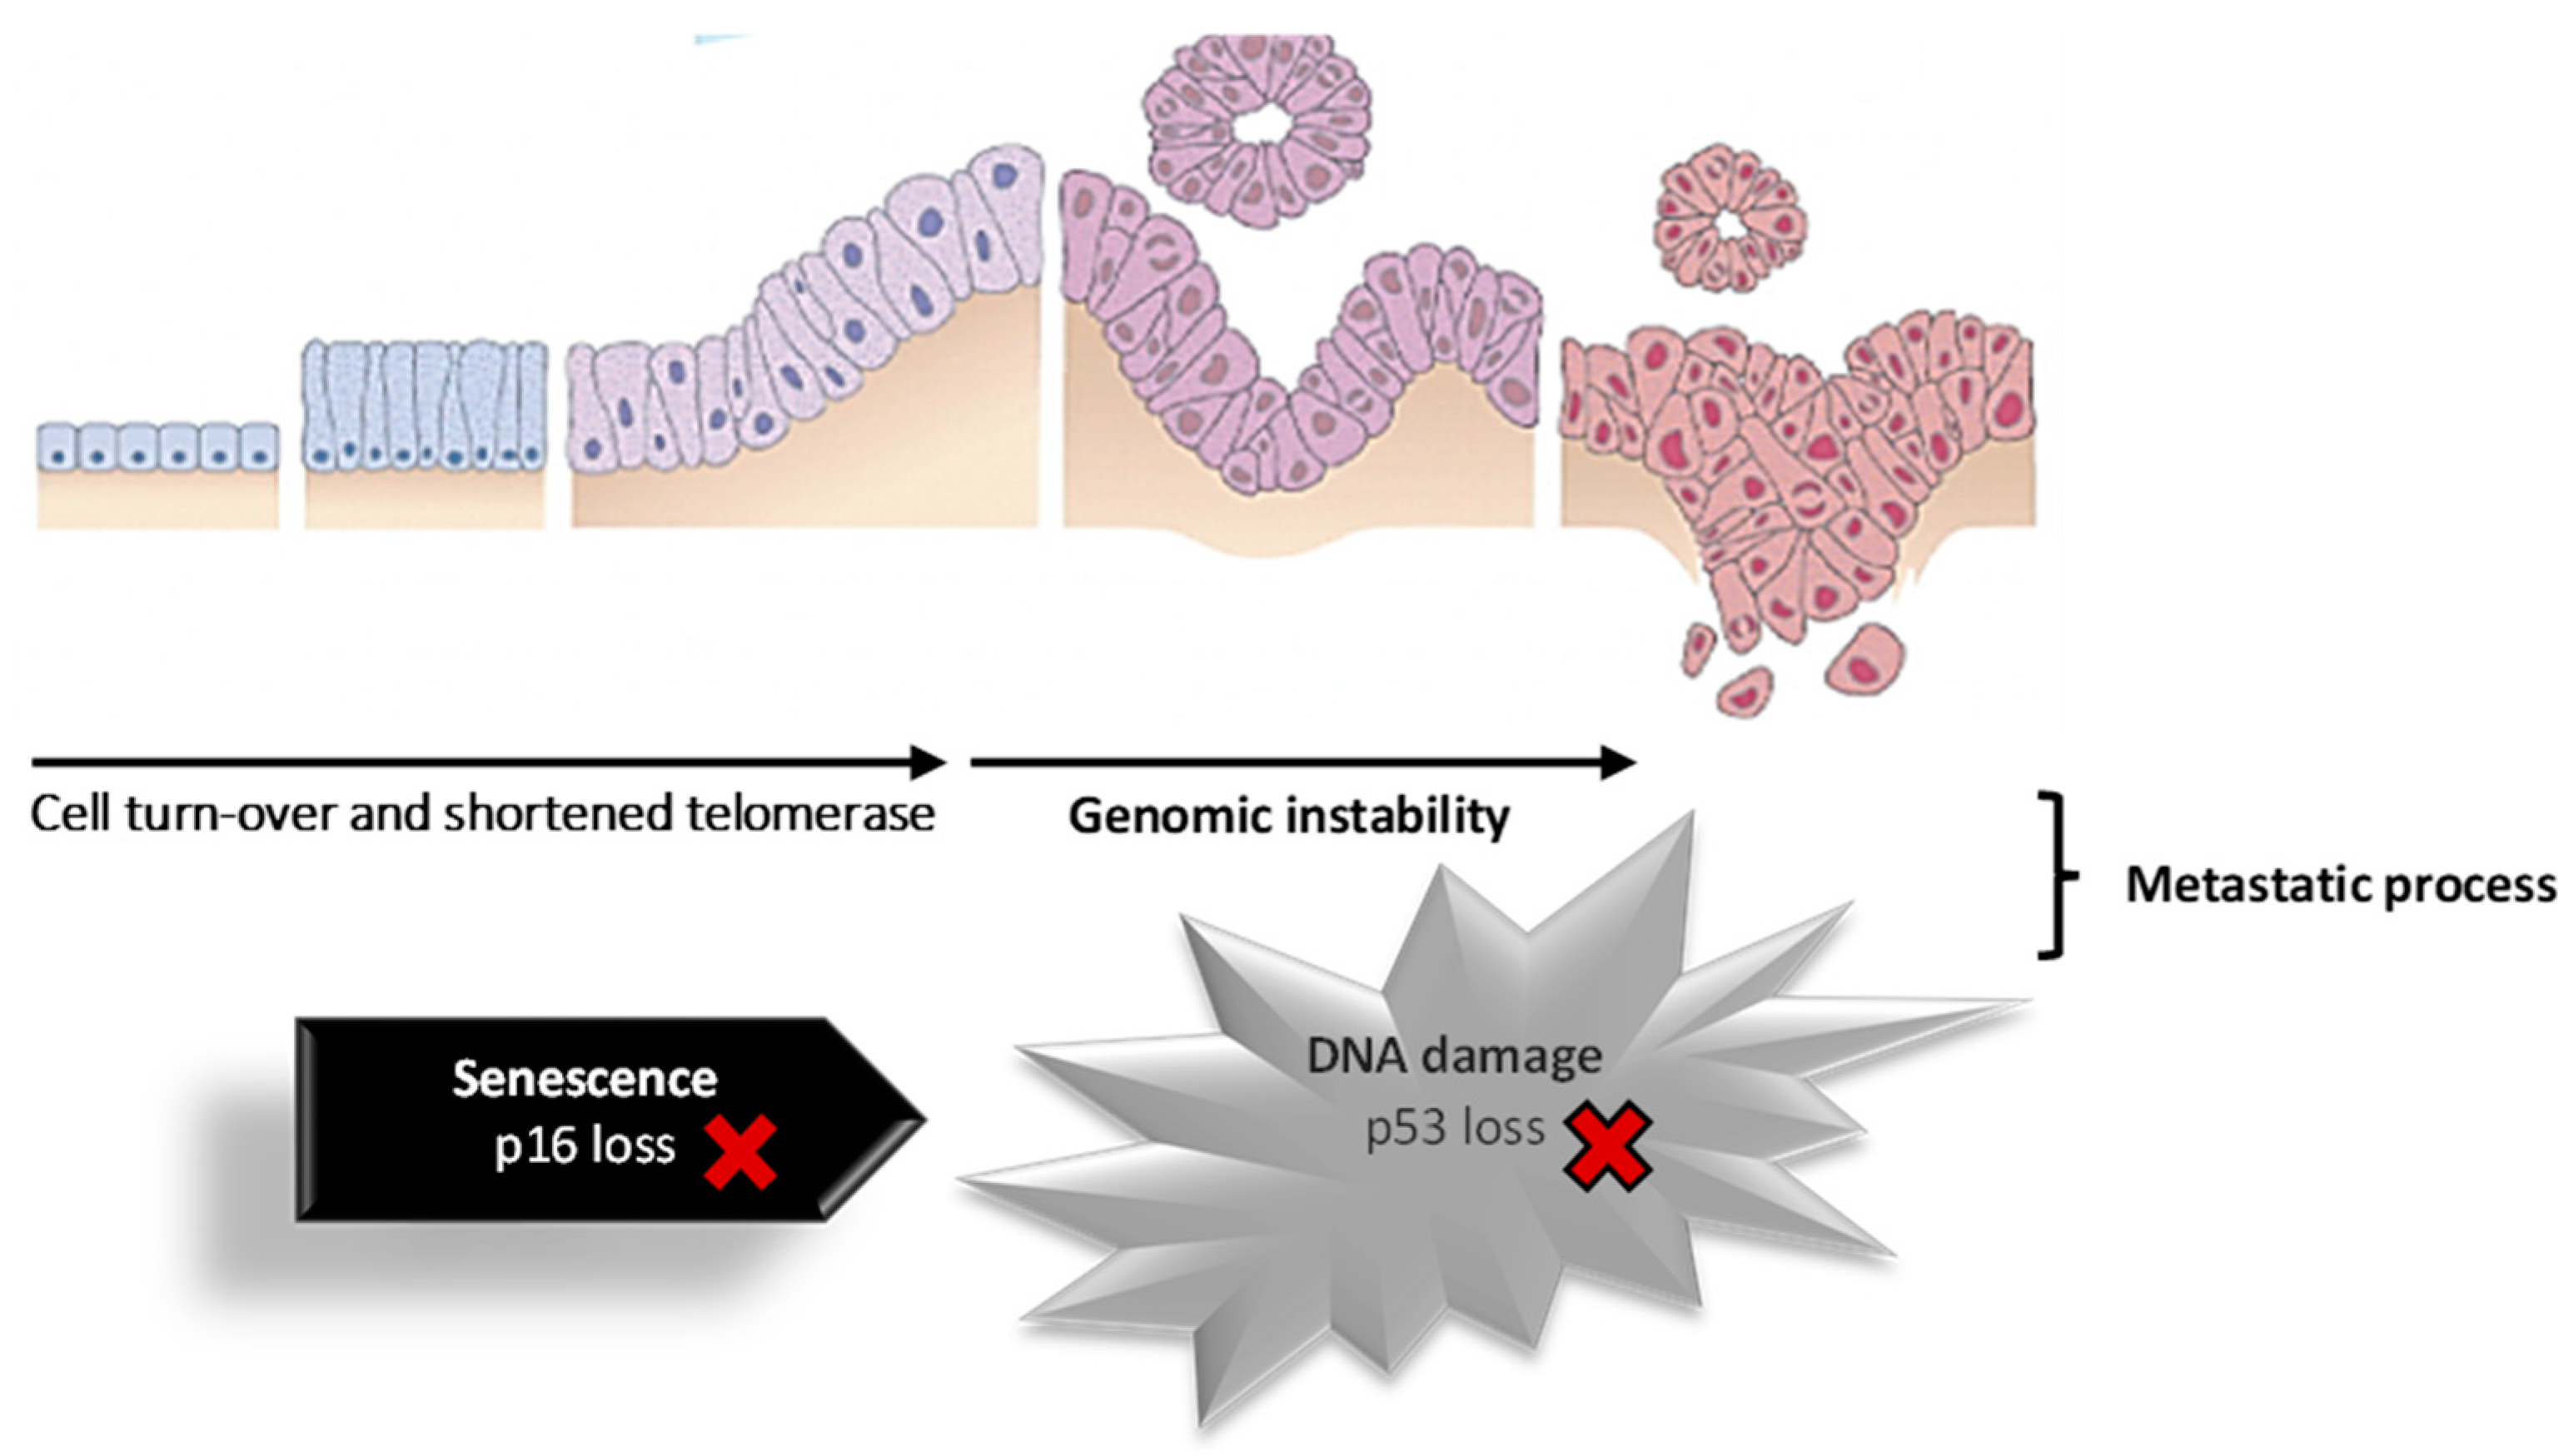

4. Pancreatic Cancer

- Gnoni, A.; Licchetta, A.; Scarpa, A.; Azzariti, A.; Brunetti, A.E.; Simone, G.; Nardulli, P.; Santini, D.; Aieta, M.; Delcuratolo, S.; et al. Carcinogenesis of Pancreatic Adenocarcinoma: Precursor Lesions. Int. J. Mol. Sci. 2013, 14, 19731–19762. [Google Scholar] [CrossRef] [PubMed]

- Iacobuzio-Donahue, C.A.; Velculescu, V.E.; Wolfgang, C.L.; Hruban, R.H. Genetic Basis of Pancreas Cancer Development and Progression: Insights from Whole-Exome and Whole-Genome Sequencing. Clin. Cancer Res. 2012, 18, 4257–4265. [Google Scholar] [CrossRef]

- Chakraborty, S.; Baine, M.J.; Sasson, A.R.; Surinder, K. Current Status of Molecular Markers for Early Detection of Sporadic Pancreatic Cancer. Biochim. Biophys. Acta BBA Rev. Cancer 2011, 1815, 44–64. [Google Scholar] [CrossRef]